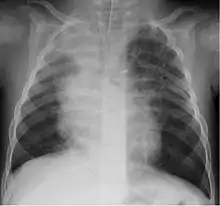

A study in Jordan found that 9% of 220 children hospitalised with lower respiratory tract infection were infected with bocavirus.[30] Of those infected the median age was 4 months. Coughing (100%), wheezing (82.7%) and fever (68.2%) were the most common clinical findings with bronchopneumonia (35%) and bronchiolitis (30%) being the most common ultimate diagnoses.

Although most cases are mild, severe respiratory disease has also been reported.[31]